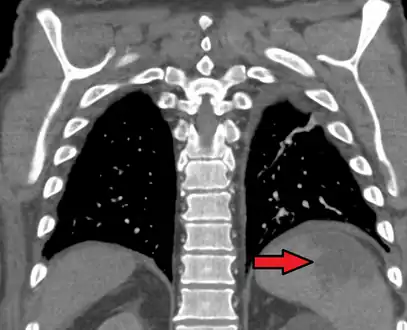

a, b) Splenic infarction.

Splenic infarct seen on CT

An abdominal CT scan is the most commonly used modality to confirm the diagnosis,[3] although abdominal ultrasound can also contribute.[16][17][18]